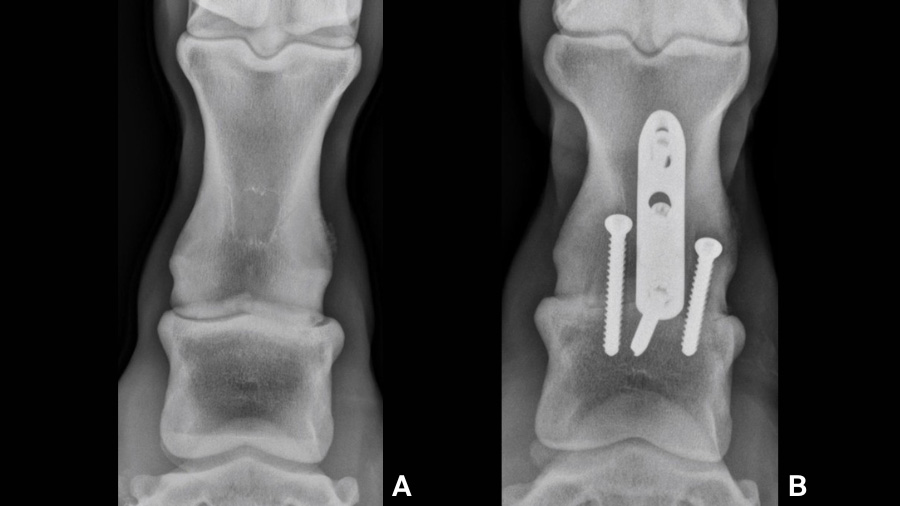

A described LST modification entails incising the dorsal joint capsule and curettage of the dorsal articular cartilage facilitated by joint distraction using elevators. In this ex-vivo report, the percentage of total cartilage removal was similar to other LST reports. Remaining cartilage was primarily in the palmar / plantar aspect of the articulation which would allow more effective apposition of the subchondral bone dorsally. In that same report, when the PIP joint was disarticulated dorsally using the standard technique, removal of 90% of the articular cartilage was achieved. In clinical cases of early to mid-stage OA, we routinely remove well over 90% of the OA cartilage by curettage (Fig. 1).

In addition, the standard approach provides adequate exposure for performing osteostixsis of the subchondral bone facilitating access to the healing elements beneath the subchondral plate. When the joint is realigned and implants are placed appropriately, excellent compression between the subchondral bone surfaces throughout the joint is attained. Compressing the subchondral plates together provides friction between the exposed subchondral bone, increasing stability to the bone-implant construct verses relying solely on the implants. Maximal stability is achieved, favoring bone healing and improving patient comfort in the early post-operative period. With the cartilage drilling LST approach, the subchondral plates will be separated by the remaining articular tissues, obviating any contact, let alone compression, between the exposed boney surfaces. The implants will provide construct stability but frictional forces will not contribute. Although it is expected that the remaining articular tissues will eventually degenerate and allow further bone formation, this is not well documented in horses. In one equine study utilizing the LC plate/screw construct combined with a single lateral to medial drill tract augmented with tissue engineering, there was considerable cartilage degeneration over the 4-month period of the study. However, when examined histologically, the tissue filling the drill tract was largely fibrous tissue with only minimal woven bone. Lastly, many patients with PIP-OA experience asymmetric cartilage loss resulting in a valgus or varus deviation at the joint. Removing the remaining articular cartilage allows realignment of the PIP joint, normalizing weight bearing forces through the digit (Fig. 2). This is expected to lessen stress on adjacent structures and contribute to positive outcomes. This is not possible with the cartilage drilling technique.